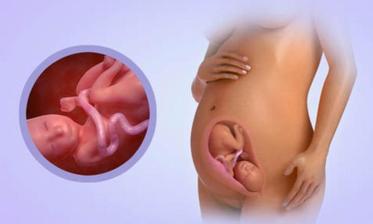

29.4. druhá KO u dr 7+3, 12,3mm a srdíčko bije

23.5. pro průkazku + odběr krve + utz 11+0 mimisek 4,2cm